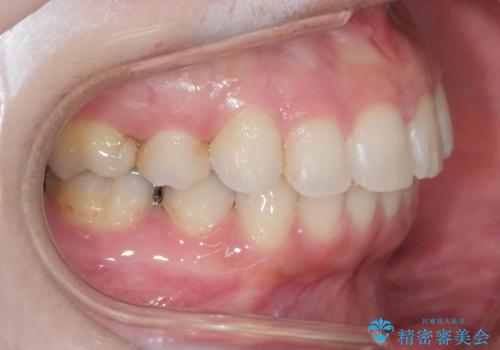

前歯のガタつきを改善 抜歯矯正後の後戻り

- 抜歯矯正後の後戻りで前歯ガタつきが主訴で来院された患者様です。

後戻りの程度としては軽度なので、治療期間としては短く終えることが出来ました。

前歯の正中線も改善され大変満足して頂きました。